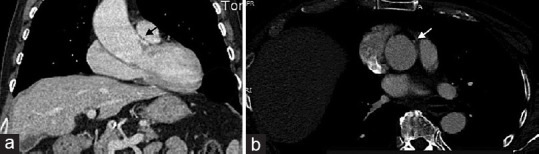

This case report presents a rare scenario involving a congenital anomaly of the right coronary artery's (RCA) origin in association with an ascending aortic aneurysm. While both anomalies are individually recognized in the literature, their coexistence and potential interplay remain understudied. The aim of this report is to emphasize the challenges and implications associated with such a combination. A 78-year-old male patient with an enlarged ascending aortic aneurysm necessitating surgical intervention was found to have an anomalous origin of the RCA during preoperative coronary angiography, confirmed by computed tomography scan. Transesophageal echocardiography further elucidated the coronary abnormality. Intraoperatively, successful aortic replacement was performed, and careful repositioning of the anomalous right coronary ostium was achieved. This case raises important considerations regarding the potential complications arising from coronary anomalies and their impact on the surgical management of ascending aortic aneurysms. The rarity of this combination limits our understanding of their association, making a multidisciplinary approach crucial for optimal patient care. Further research and comprehensive evaluation of similar cases are necessary to better understand the relationship between coronary anomalies and ascending aortic aneurysms. Such investigations will help in improving treatment strategies and outcomes for patients with these complex conditions.